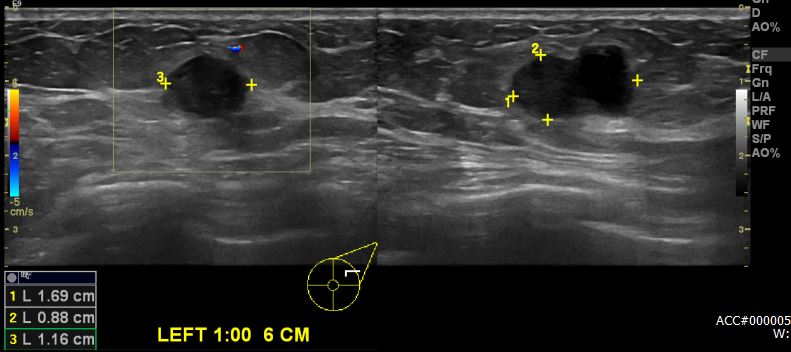

상기환자 건강검진상 이상 소견으로 내원하신 50대 여성분으로 본원 초음파상 좌측 1시

방향에서 6cm 떨어진 거리의 의심 스러운 혹 조직검사 시행하여 좌측 친윤성 유관암 진단되었습니다.